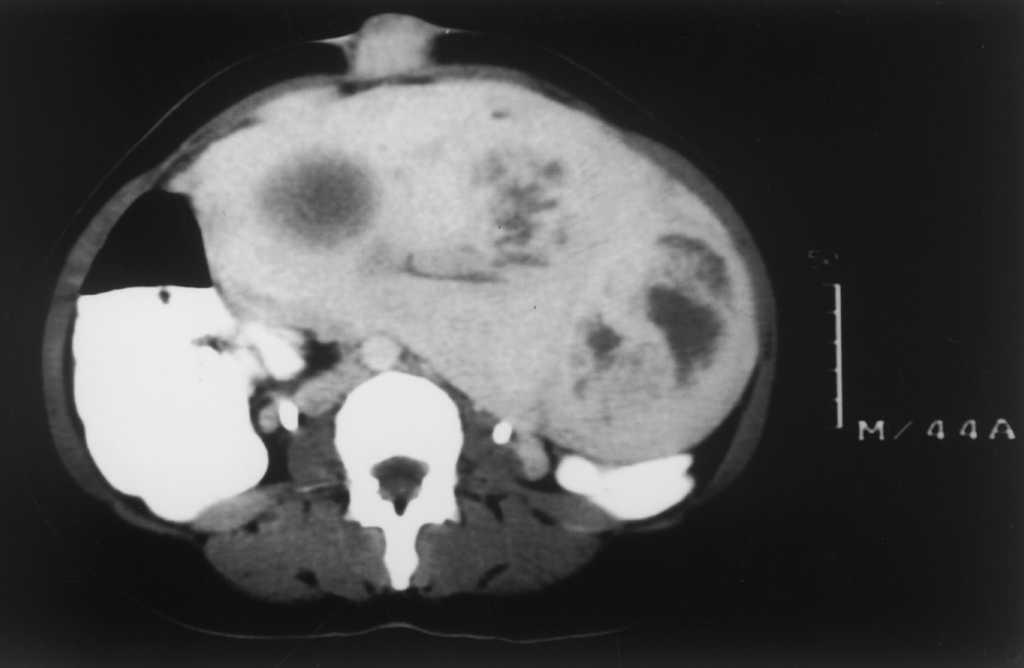

A la exploración se apreció una lesión dura, de 4 x 3 cm de diámetro, color marrón azulada, desplazable con facilidad sobre planos profundos y ligeramente dolorosa a la palpación (fig. 2). Se realizó una biopsia, y en el estudio histopatológico se observó una lesión cupuliforme, cercana a la epidermis caracterizada por formaciones glandulares en el seno de una estroma mixoide muy vascularizada (fig. 3). En la estroma se apreciaban focos microscópicos de extravasación hemática. Las estructuras glandulares estaban tapizadas por células epiteliales, que mostraban secreción por decapitación (fig. 4). Las luces glandulares eran ovaladas o anguladas aunque algunas estaban rotas y desestructuradas.

Fig. 3.--Glándula en el seno de la estroma mixoide muy vascularizada.

Fig. 4.--Glándulas tapizadas por células epiteliales con secreción por decapitación.

El estudio histopatológico encuentra glándulas en la estroma celular en la que se aprecia extravasación hemática. Las luces glandulares pueden ser redondas, alargadas o anguladas, pueden contener detritos celulares, eritrocitos y un material amorfo PAS (ácido peryódico de Schiff) y azul alcián positivo. Se localizan en dermis y/o tejido celular subcutáneo. Al igual que el endometrio, los hallazgos histopatológicos pueden variar según las distintas fases del ciclo menstrual. De este modo, en la fase proliferativa existe una pronunciada actividad mitótica, que confiere al epitelio un aspecto pseudoestratificado. En la fase secretora se aprecia una secreción por decapitación de las células glandulares. En esta fase suelen evidenciarse dos tipos celulares en la estroma: una célula grande de citoplasma amplio y otra célula clara de menor tamaño, que equivaldrían a las células predeciduales y al granulocito endometrial. Finalmente, en la fase menstrual, es típica la desintegración del epitelio glandular. Sin embargo, no suele existir una buena correlación entre los cambios histológicos de la endometriosis y la fase del ciclo menstrual en que se halle la paciente4,15-17. Incluso se pueden observar glándulas en distintas fases del ciclo menstrual en una misma paciente17. En casos dudosos la presencia de receptores estrogénicos en las células del epitelio glandular apoyará el diagnóstico de endometriosis18.